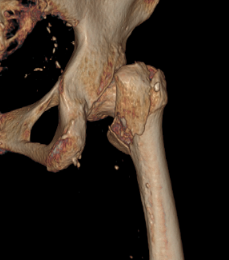

经详细检查,应奶奶被确诊为“右侧股骨粗隆间骨折”。这种骨折常被称为“人生最后一次骨折”,对于百岁超高龄老人而言,风险极高——长期卧床可能迅速引发肺部感染、深静脉血栓、褥疮等一系列致命并发症,保守治疗风险巨大。

骨科团队迅速评估病情,认为手术治疗是让老人重新站起来的唯一希望,也是降低长期卧床并发症风险的最佳选择。在科主任李忠教授带领下,唐炼副主任医师团队反复研究影像资料,精心设计创伤小、固定可靠的手术方案——微创闭合复位股骨近端防旋髓内钉(PFNA)内固定术。手术仅用时30分钟顺利完成。